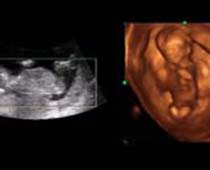

- Fetal Face Ultrasound Photos

- 3D Fetal Profile Ultrasound Scan Photos

- The Clinical Advantages of 3D and 4D Ultrasound

- Definition and Features of Four Dimensional Ultrasound

- Uses of 4D Ultrasound scan